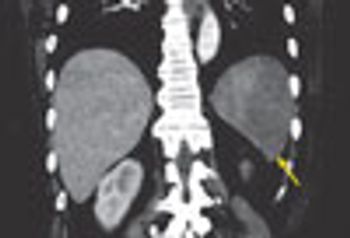

A 53-year-old woman presented with sudden onset of left upper quadrant abdominal pain. She had a history of atrial fibrillation, hypertension, and congestive heart failure.